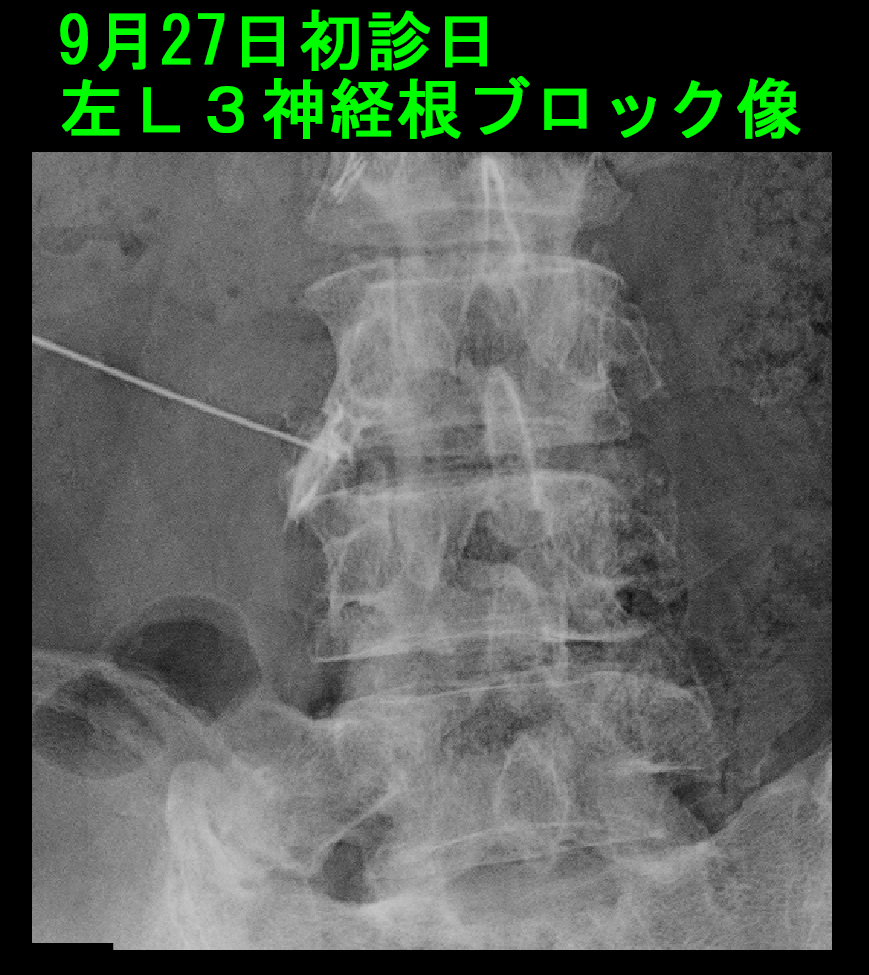

椎間板ヘルニアではこの場合にはL3神経根という神経にブロックを行うのが一般的です。初診日に左L3神経根ブロックを施行しました。

75才男XpRB1.jpg